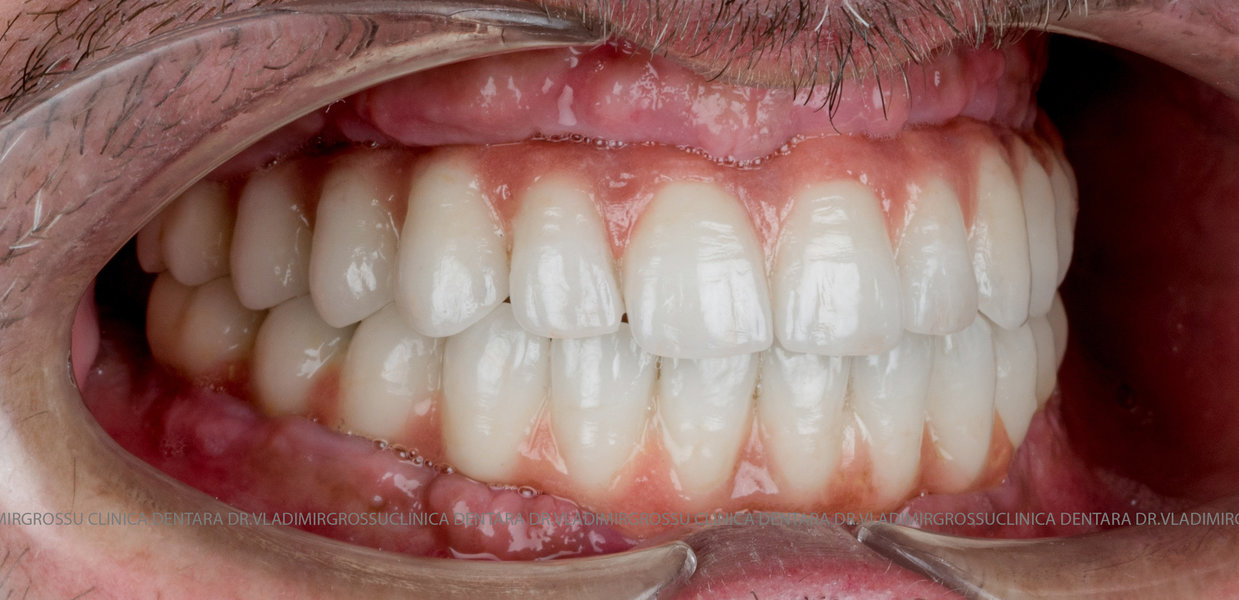

Cazuri clinice conceptul All-on-6